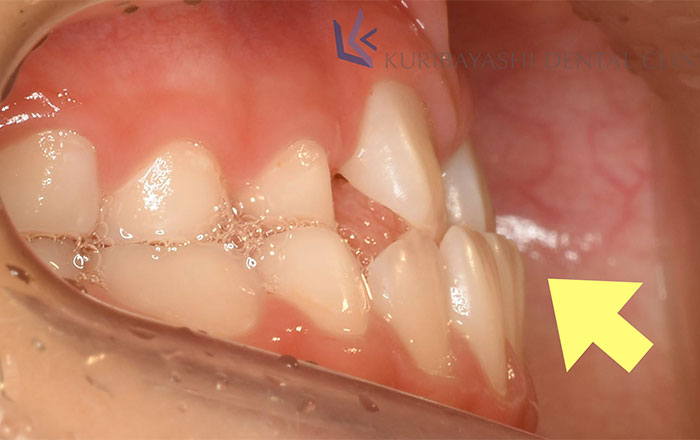

重篤な【受け口】などの状態も、骨の成長過程の子供のうちは骨の矯正も行えます。

10歳頃までに上顎の成長が止まると言われているので、成長が止まるまでの間に上顎が下顎を乗り越えることが望ましいです。

成長が止まった上顎が下顎のストッパーになります。

上顎の成長が止まる前に矯正を行うことで、受け口などの重篤な状態でも、矯正治療のみで行える可能性が高くなります。

この歯並びを改善しないままだと、ストッパーとなる上顎がいないので、下顎が成長し続け、どんどん下顎が拡大していきます。